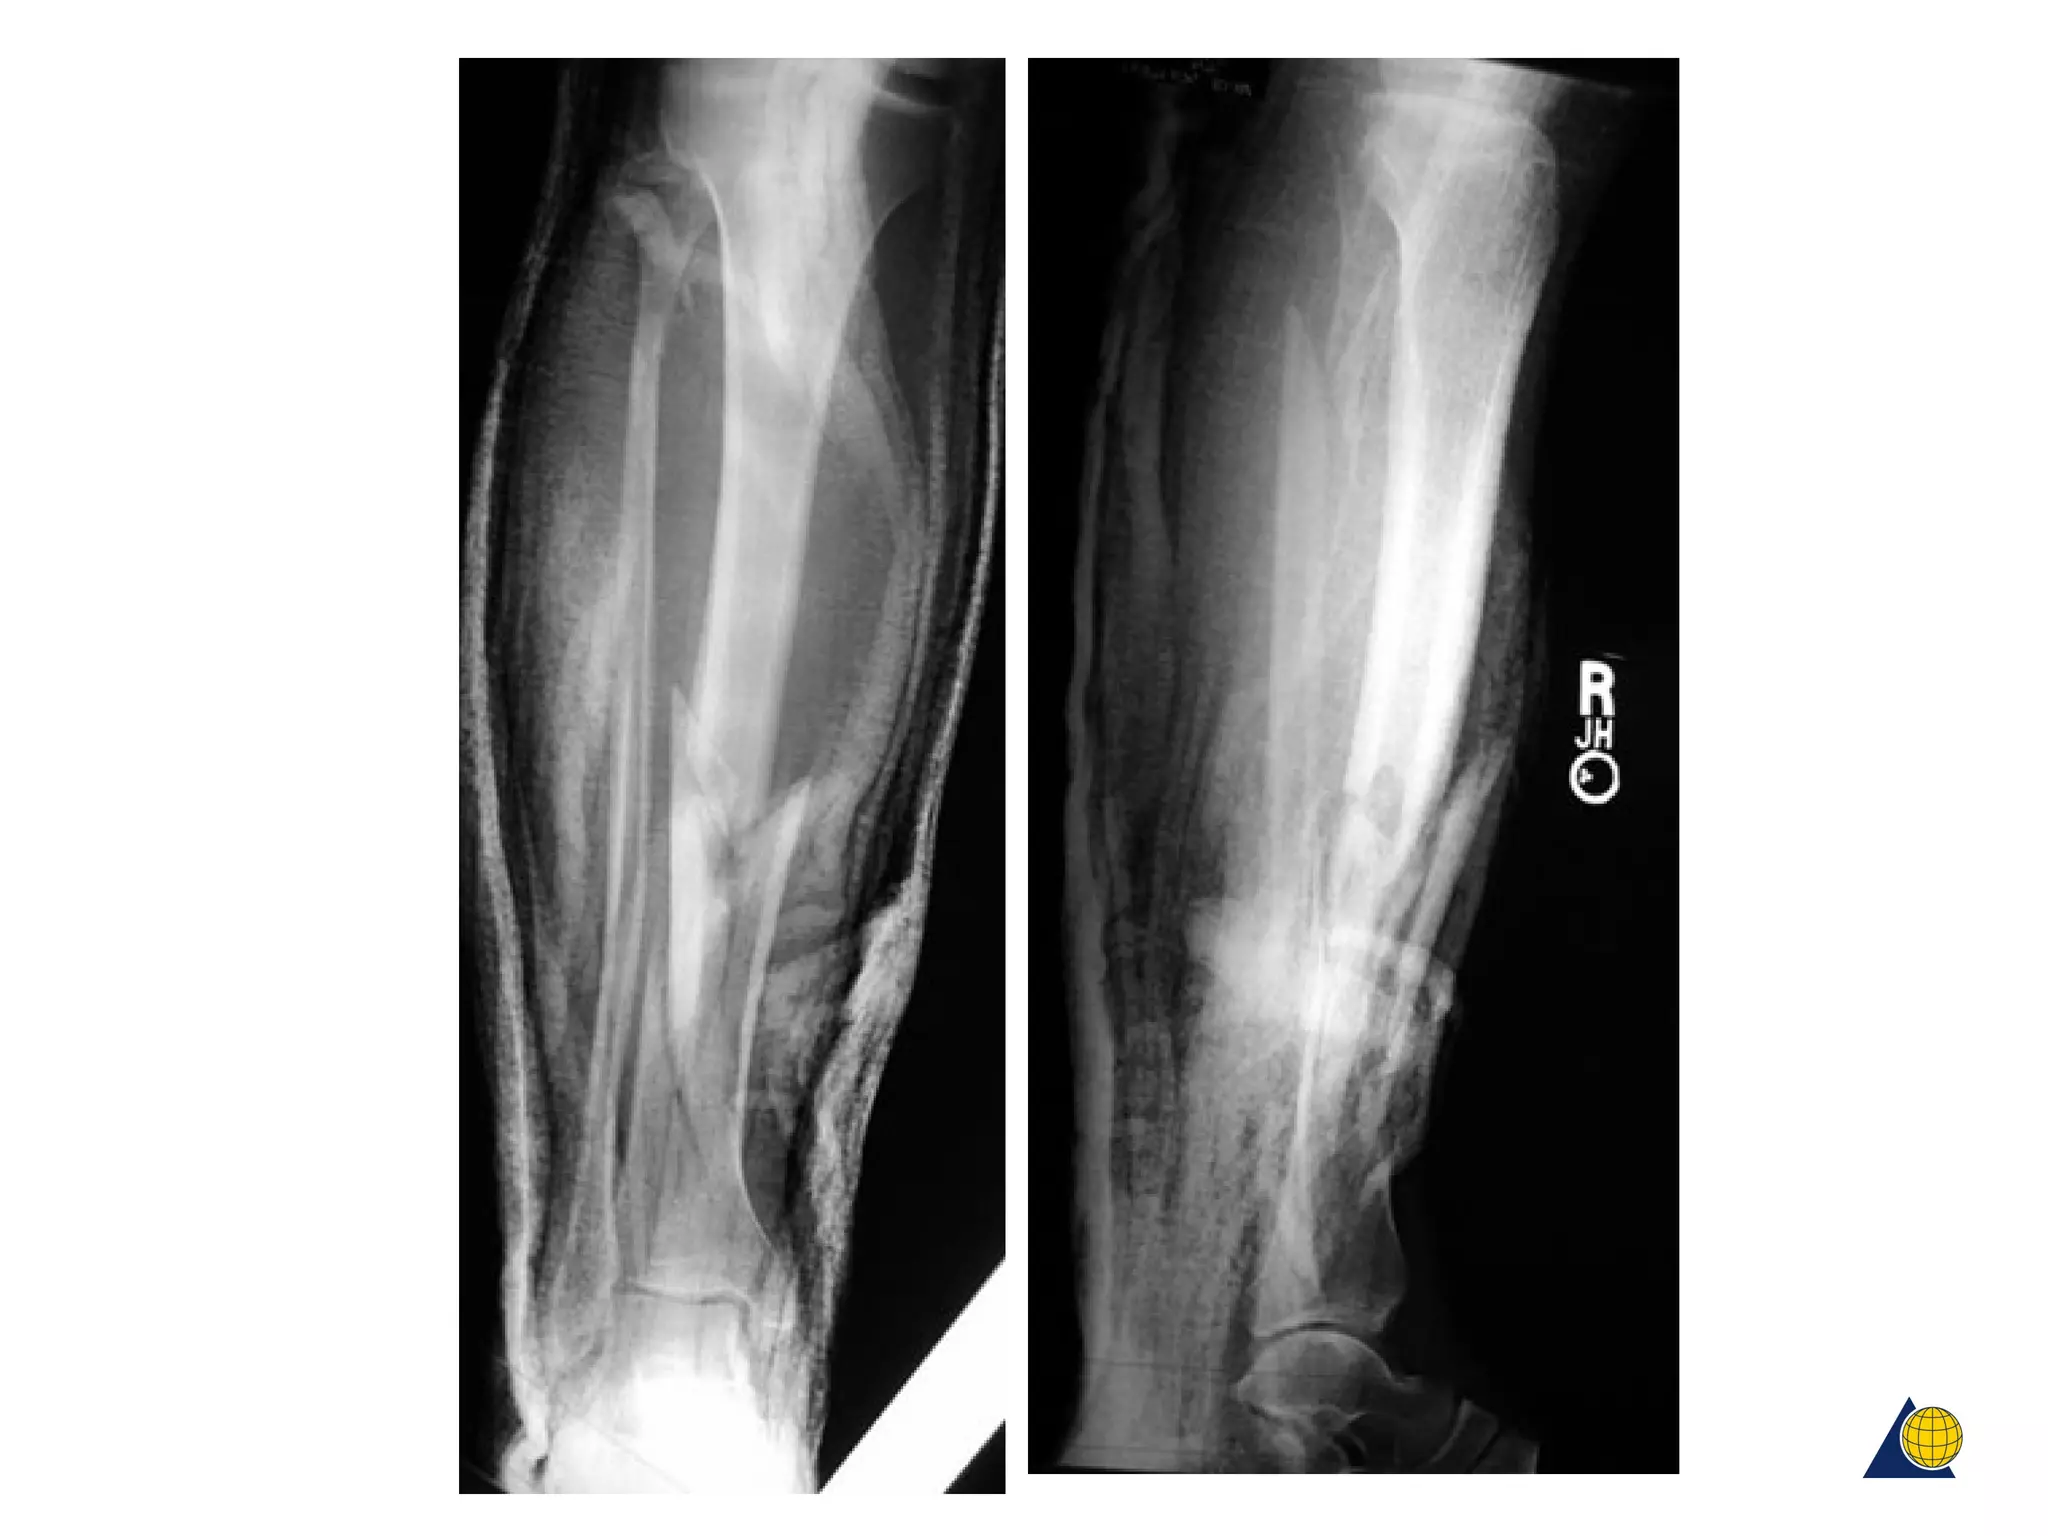

• Multifragmentary

diaphyseal fractures

metaphyseal fractures

• Not amenable to anatomical

reduction and absolute stability